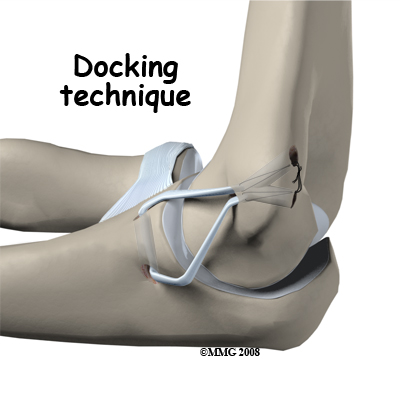

If the ulnar collateral ligament has been injured acutely due to a fall on the outstretched arm, a direct repair of the ligament may be possible. If the ligament has pulled off the bone, it may be reattached with sutures through holes drilled in the bone. If the ligament is damaged by constant overuse and is not strong enough to restore stability to the elbow joint if it is simply re-attached or repaired, then the ligament must be replaced with a new ligament. This is termed a ligament reconstruction. During a reconstruction, the ulnar collateral ligament along the medial (inside) of the elbow is replaced with a tendon graft harvested from somewhere else in the body (autograft). One common technique used to replace the damaged ulnar collateral ligament is called the technique.